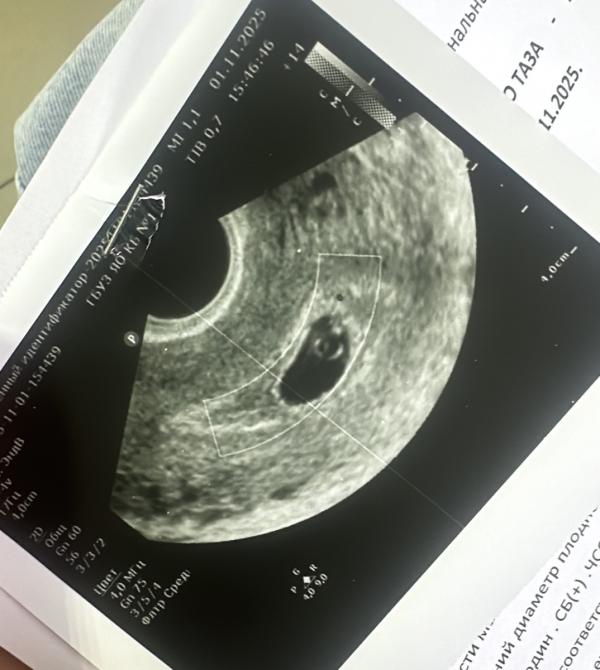

5,5 недель

Ктр 2 мм

Сердцебиение слабое. 90 ударов